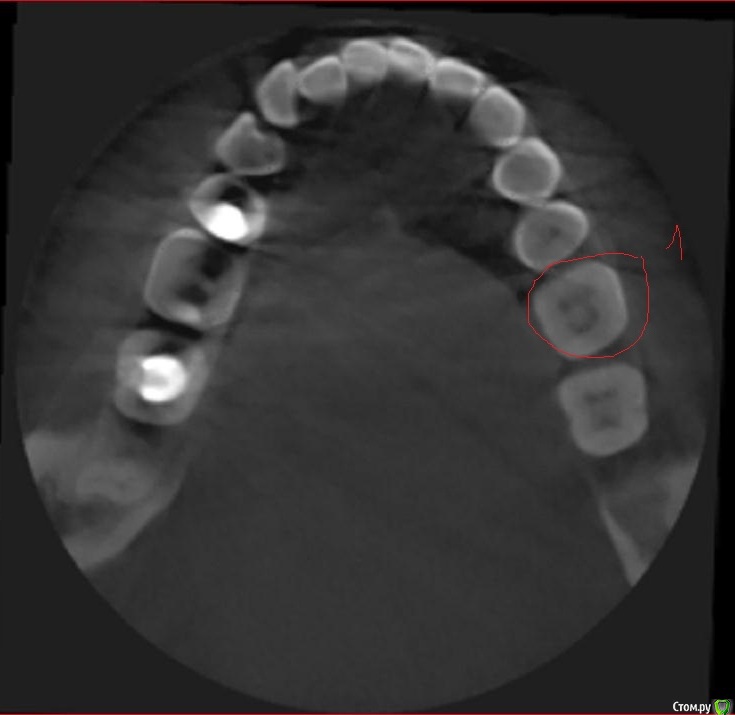

Svetic Опубликовано 16 августа, 2015 Поделиться Опубликовано 16 августа, 2015 (изменено) Здравствуйте, история такая. Отправилась лечить нижнюю шестерку. Выпала пломба, зуб реагировал на холодное и на накусываение. Врач поставила пломбу,депульпировать не стала. Зуб заболел через два дня. Четыре дня назад удалили нерв, реакция зуба на холодное осталась. Позвонила по телефону врачу, говорит что после мышьяка болеть зуб не может. Мог ли врач пропустить один канал? Нашла томограму которую делала 3 месяца назад. Скажите пожалуйста сколько в шестерках каналов? Врач пролечила 3 канала. Тот зуб под номером 1 еще до лечения. Изменено 16 августа, 2015 пользователем Svetic Ссылка на комментарий

St. Опубликовано 16 августа, 2015 Поделиться Опубликовано 16 августа, 2015 Каналов 4. КТ доктор во время лечения видел? Ссылка на комментарий

St. Опубликовано 17 августа, 2015 Поделиться Опубликовано 17 августа, 2015 Искать и долечивать пропущенный канал. Ссылка на комментарий